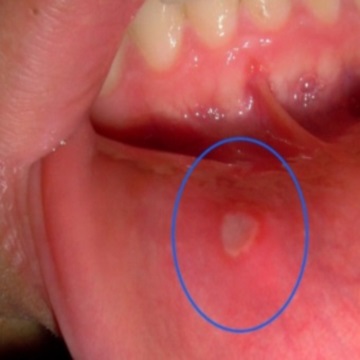

1. 아프타성 구내염

가장 많은 수를 차지하고 있습니다. 궤양성이라 부르기도 하는데 하얗거나 노르스름한 막으로 덮힌 염증이며 이 주변은 빨간 테두리가 보입니다. 뺨 안쪽, 혀, 잇몸, 입술 안쪽에 생기기 쉽고 1~2주 정도면 자연스럽게 개선되는 경향이 많습니다.

음식을 섭취하거나 음료를 마시면 쓰리면서 아린 증상이 나타납니다. 원인은 면역력 저하, 과로, 영양부족, 수면부족, 스트레스, 호르몬 불균형, 생리전, 임신 등으로 볼 수 있는데 면역력이 떨어져 있을 때 걸리기 쉽습니다.